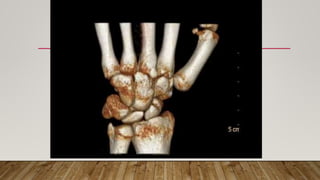

This document discusses radiology and the use of x-rays. It begins with an introduction to radiology and x-rays, noting their importance as the "father of medical investigations." It then discusses anatomy as seen on radiographs and whether x-rays are enough. The document goes on to compare gross views to radiological views, noting what each can and cannot show. It highlights important figures in the development of radiology, from x-rays to CT, MRI, and ultrasound. Specific anatomical structures visible on upper and lower limb x-rays are listed. The document concludes by discussing how pathologies appear on x-rays and the importance of clinical history and knowledge when interpreting radiological images.